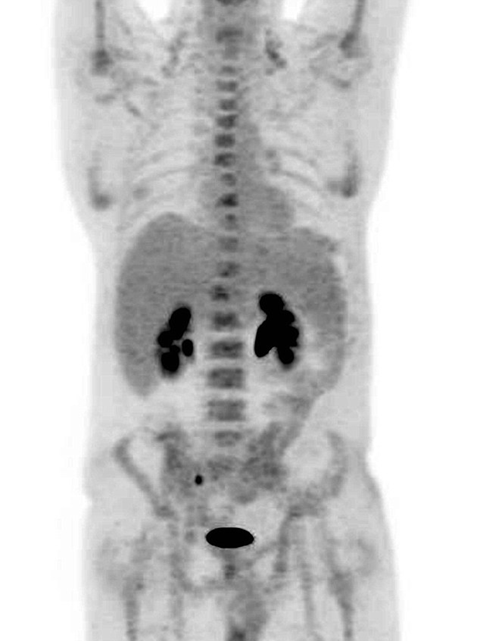

Ngoài ra, vết đậm trong thận và bàng quang của ông chứng tỏ chúng cũng hoạt động hoàn toàn bình thường. Sau vài ngày theo dõi tại bệnh viện, sức khỏe của Ian đã hoàn toàn bình phục để có thể xuất viện.